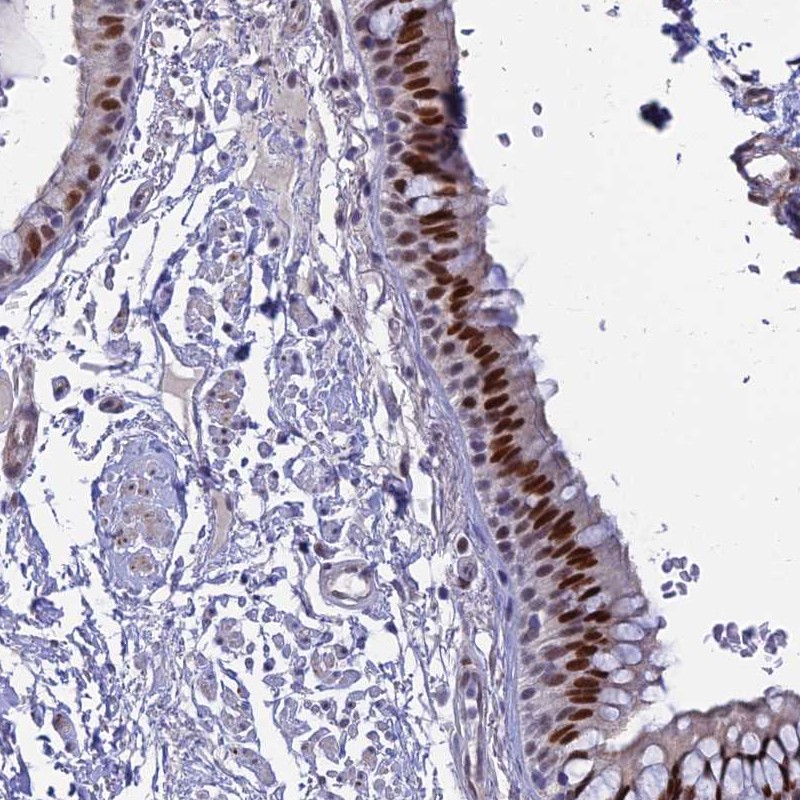

Immunohistochemical staining of human bronchus shows strong nuclear positivity in respiratory epithelial cells.